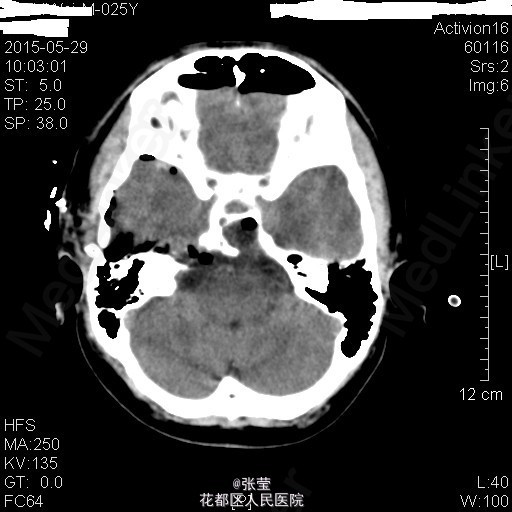

青年男性,主诉:头晕伴肢体乏力1周。 现病史:患者1周前始无明显诱因反复出现头晕,伴左侧肢体乏力、行走不稳,偶伴头痛、恶心感,休息后可稍缓解,无呕吐,无天旋地转感,无晕厥,无伴听力、记忆力减退等,发作无明显规律。至当地医院就诊,头部MR结果示:右间脑下方-脑干-桥前池-左鞍底区肿瘤,并瘤内卒中。

查体:神清,对答切题,双瞳等大等圆,直径约3mm,对光反射灵敏,双侧听力粗测正常,四肢肌力Ⅴ级。生理反射存在,病理征未引出。 辅查:颅脑MR:1、斜坡区占位,侵及中脑、脑桥右份及蝶窦,病灶ADC值增高,FA值下降,考虑脊索瘤并囊变、出血可能大。 2、MRA示双侧颈内动脉向外侧移位,余脑动脉未见明确异常。

患者入院后完善相关检查,排除手术禁忌症,于2015年4月7日行"神经内镜下经鼻蝶入路斜坡脑干占位病变切除+鞍底重建+左下腹脂肪取出术",手术顺利。 术后病理示:脊索瘤。 予抗感染、护胃、化痰、维持水电解质平衡及加强营养支持治疗,患者病情较前明显好转。